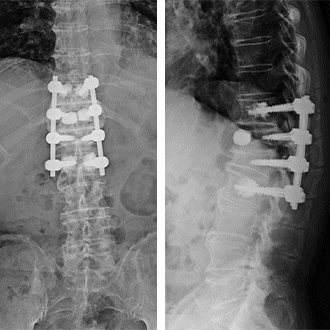

2. 成人脊柱変形に対する変形矯正手術

脊柱変形矯正手術は、脊椎外科の中でも最も難易度の高い手術のひとつとして位置づけられています。当院では脊柱変形疾患における代表的手術である脊柱変形矯正手術に取り組んでいます。近年ではLLIF(5.を参照してください)といわれる固定術が導入され手術が低侵襲化され、80歳代の高齢の方でも条件が合えば手術を選択することが出来るようになりました。

手術によって前傾姿勢が改善して問題なく歩行ができるようになりました。